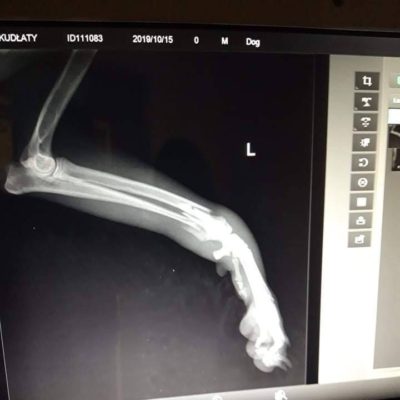

„Opiekunka” stwierdziła, że kundla leczyć nie będzie. To tylko pies. Co z tego, że ma pogruchotaną łapę i cierpi? Pani się psa zrzeka i można go uśpić, albo można go oddać, ona ma to gdzieś.

Nie mogliśmy pozwolić maluchowi na cierpienie. Zabraliśmy go do siebie i chcieliśmy poddać operacji. Taka operacja to koszt 3500 zł… Nie mamy tyle.